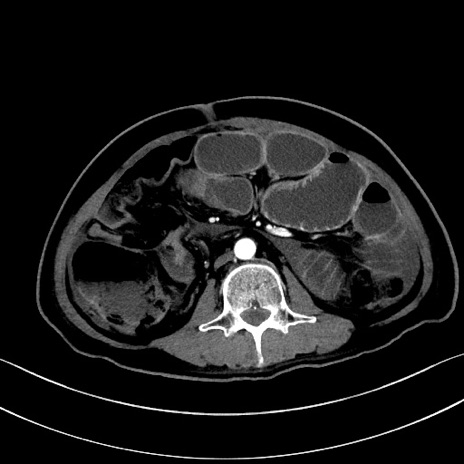

症例28(横断像)

【症例】60歳代男性

【主訴】嘔吐

【現病歴】胃癌にて胃全摘後。食思不振が悪化し、夜中に嘔吐することがある。

【既往歴】胃癌、胃全摘、脾摘、胆摘後

【データ】WBC 5900、CRP 10.56